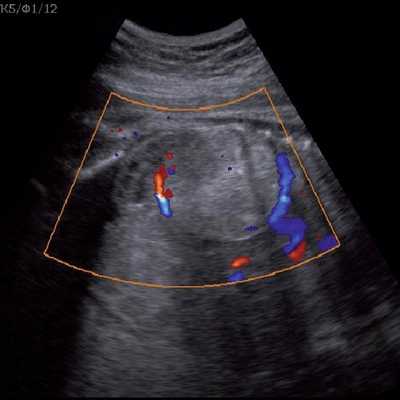

Под диафрагмой справа визуализировалось гиперэхогенное опухолевидное образование несколько неоднородной солидной структуры, с четкими ровными контурами, размером 50x38x35 мм. К нижнему полюсу данного образования прилежала правая почка, имеющая нормальные размеры, форму и структуру. Нижняя полая вена была смещена кпереди и влево. Обращала на себя внимание выраженная гепатомегалия, причем структура печени не была однородной. Она содержала множественные гиперэхогенные включения размерами до 17 мм, окруженные тонким гипоэхогенным периферическим ободком. Цветовое допплеровское картирование(ЦДК) демонстрировало интенсивную периферическую васкуляризацию опухоли (рис. 1-3).

Рис. 2. Кровоток в нейробластоме плода. Цветовое допплеровское картирование. Отчетливо виден питающий сосуд, огибающий образование по его периферии. К нижнему полюсу образования прилежит интактная почка плода.

Рис. 3. Метастазы в печени плода. Поперечное сечение брюшной полости плода. Гепатомегалия. В структуре печени плода определяются округлые включения несколько повышенной эхогенности (стрелки), с гипоэхогенным ободком - метастазы.

Цветовое допплеровское картирование помогает идентифицировать питающий опухоль сосуд, отходящий непосредственно от аорты, однако такой единственный сосуд может и не визуализироваться [13].